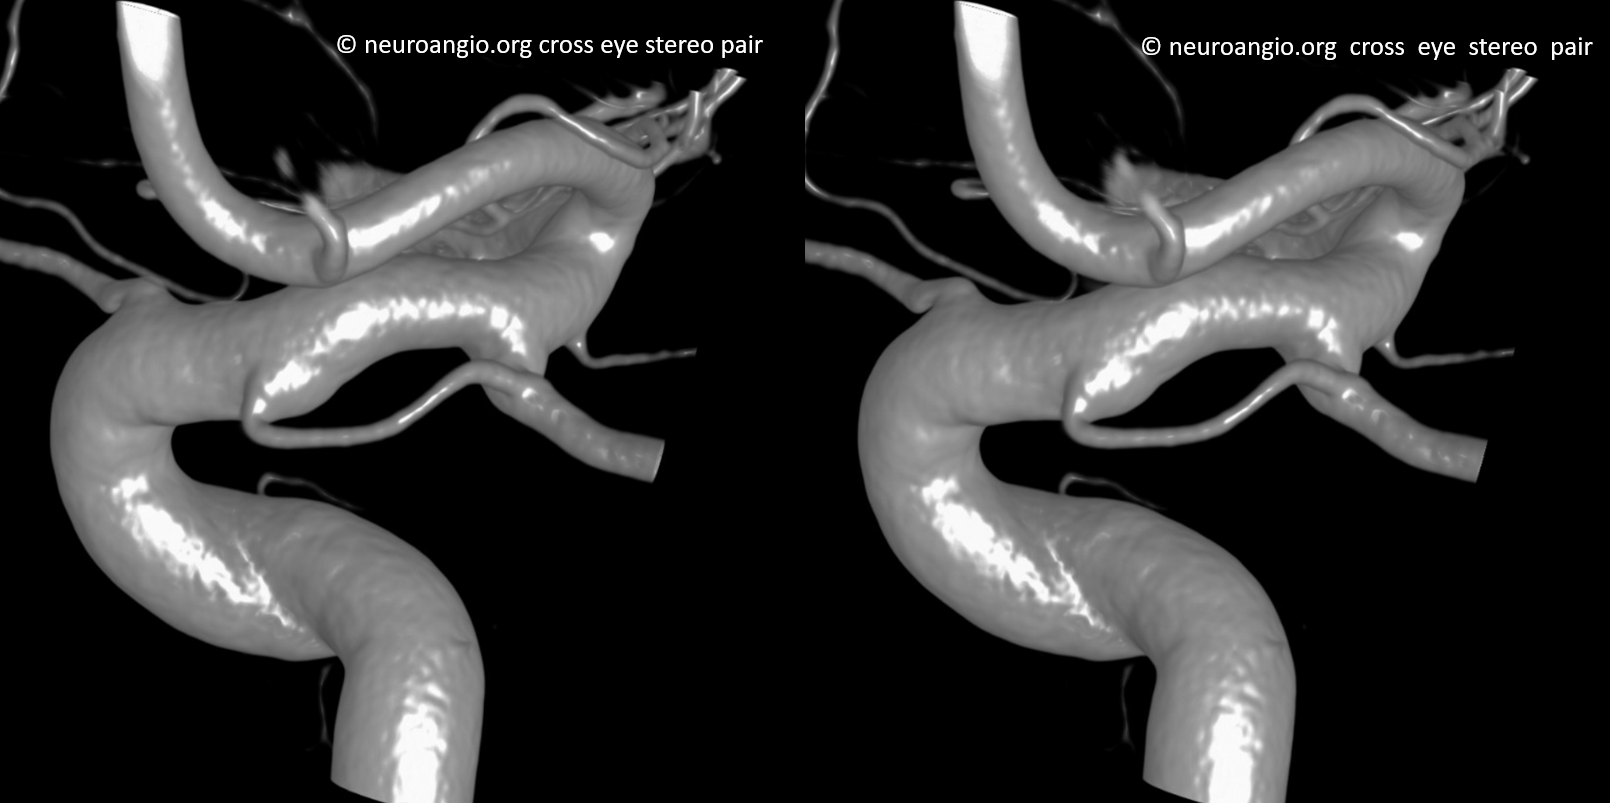

Stereos and MIPs. Both superior and inferior hypophyseals are well seen. The superior hypophyseal, despite being invisible on standard issue views, is quite large, even having two branches to the hypophysis.

Case courtesy Dr. Eytan Raz — here is a beautiful example of a very dominant superior hypophyseal artery (arrow) supplying the posterior hypophysis (arrowhead), with a correspondingly small inferior hypophyseal contribution from the MHT (dashed arrow)

Cross eye stereo

View from the back — again small inferior hypophyseal, big superior hypophyseal — balance again… See the beautiful vascular ring of the posterior pituitary — the connecting it with the contralateral side

Cross-eye stereo

MIP image shows the sella nicely — and helps prove its posterior pituitary

Of course, there is an aneurysm here — the branch point camp would point out how this larger than usual branch is a setup for aneurysmal formation. Naturally…